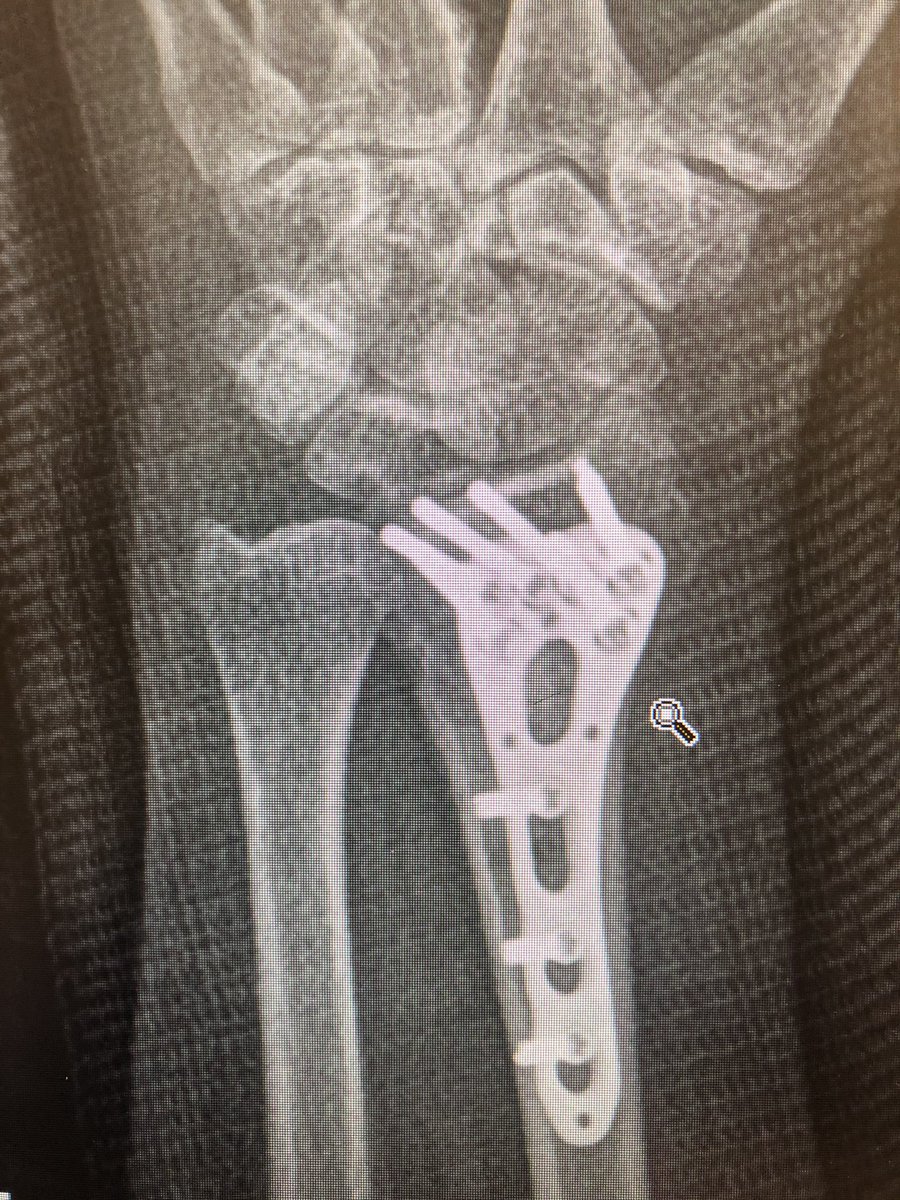

Point 3: the tangential view.

The wrist flexed ‘dorsal tangential view’ or as we locally call it ‘Lleyton Hewitt View’ is increasingly popular (published from our institutes with my colleagues too), but I find the ‘extended tangential’ or ‘DRUJ View’ more informative.

As compared to the dorsal tangential view, this DRUJ view gives better light contrast to view the dorsal rim and also additional information about the DRUJ to make sure there is no screw protrusion into the ulnar notch.

This was the patient at 2 weeks. Already on range of motion. The flat lateral X-ray always looks like the screws are in the joint. That’s because of the distal radius joint inclination angle.

Take intra-operative 20 degree elevated lateral shot to see through the joint.